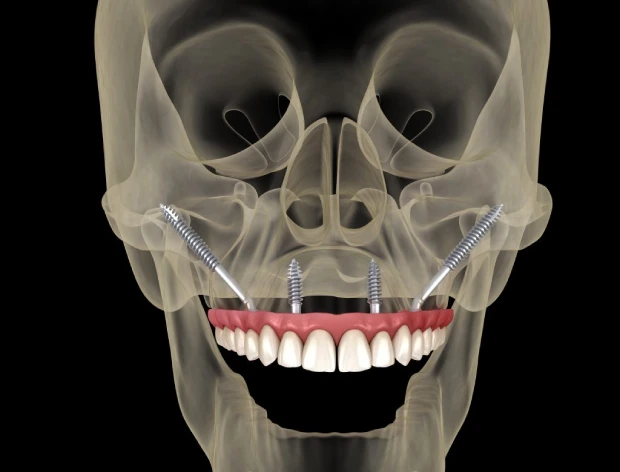

Los implantes cigomáticos son un tipo de implante dental especialmente diseñado para pacientes que no tienen suficiente hueso en el maxilar superior. A diferencia de un implante convencional, que se fija en el hueso del maxilar, el implante cigomático es más largo y se ancla en el hueso cigomático (el pómulo), una zona muy densa y estable que siempre mantiene suficiente estructura ósea, incluso cuando el maxilar está muy reabsorbido.

El número de implantes cigomáticos necesarios suele variar entre 1 y 4 por arcada y depende principalmente de la calidad del hueso maxilar y la calidad del hueso cigomático (pómulo). Cuando el hueso del maxilar no es suficiente, utilizamos el hueso cigomático (el pómulo) como punto de anclaje.

Si la pérdida ósea solo afecta a una parte del maxilar, es posible colocar un solo implante cigomático en la zona con peor hueso y completar el resto de la sujeción con implantes tradicionales, que es una cirugía más sencilla y más económica.

Sin embargo, cuando no existe buen hueso maxilar en ninguna zona, o incluso cuando el punto de apoyo en el pómulo no ofrece la estabilidad ideal, pueden necesitarse hasta 4 implantes cigomáticos para conseguir una fijación segura y permitir una rehabilitación fija inmediata.

Sí. Los implantes cigomáticos pueden sostener una prótesis fija completa en el maxilar superior. Suelen combinarse con otros implantes adicionales para crear una estructura estable que permita una rehabilitación fija, incluso cuando el paciente no tiene hueso en absoluto.

Un implante cigomático mide entre 35 mm y 55 mm, mucho más que un implante dental convencional, que suele medir entre 8 y 18 mm. Su longitud permite alcanzar el hueso del pómulo para ofrecer la estabilidad necesaria en casos de atrofia ósea severa.